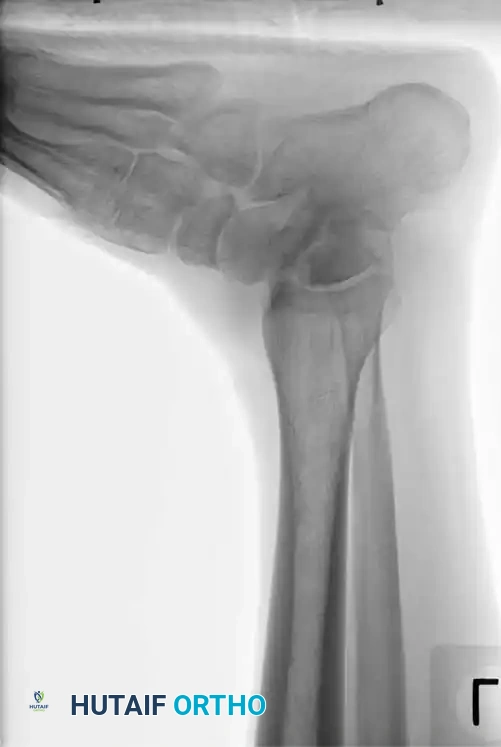

Avascular Necrosis (AVN) and the Hawkins Sign

The most feared complication of talar neck fractures is AVN of the talar body. At 6 to 8 weeks post-injury, an AP or mortise radiograph of the ankle should be scrutinized for the Hawkins Sign.

The Hawkins sign is a subchondral radiolucent band visible in the dome of the talus. This radiolucency represents subchondral osteopenia secondary to hyperemic bone resorption. The presence of a Hawkins sign is a highly reliable indicator that the talar body retains its vascular supply. Conversely, a sclerotic, radiodense talar dome at 8 weeks indicates AVN.